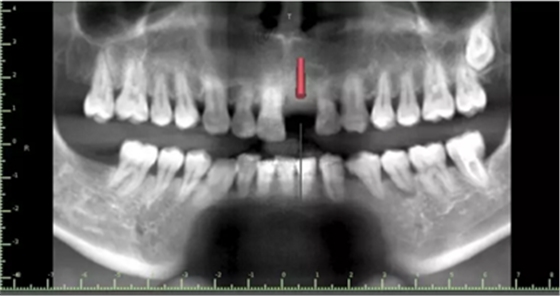

1.術(shù)前CT

2.術(shù)前植體設(shè)計(jì)